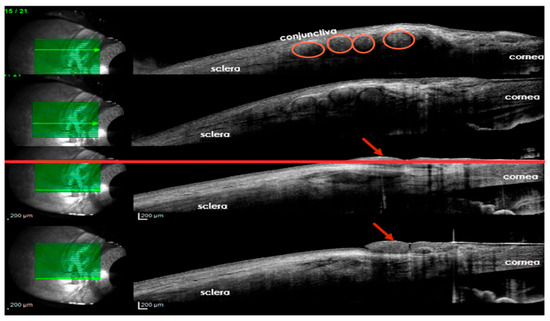

Outcome measurement is another challenge that surgeons face. IVCM is not easily accessible, and the CBA has some degree of subjectivity. Pain, ultimately, is a subjective experience, so improvements in sensitivity scoring may benefit only the scientific community and not the patient. Standardized outcome reporting across studies is crucial to ensure comparability and consistency in assessing the effectiveness of corneal neurotization. Additionally, long-term neurophysiological assessments could provide insights into the durability of nerve regeneration and functional recovery over time. We suggest that the presence of nerve filaments tunneled around the cornea could be observed using optical coherence tomography (OCT) (Figure 4). Refinements in anterior segment OCT could improve nerve fiber detection at the level of the corneal sub-basal plexus.

Figure 4. Ocular coherence tomography, 3 years after corneal neurotization, demonstrates the presence of nerve grafts beneath the conjunctiva (circles) at the level of the peripheral cornea (arrows) (personal archive, Samoila Ovidiu).